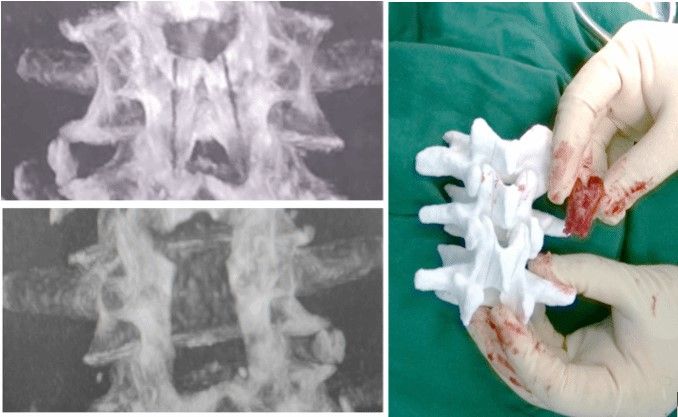

On July 16, 2023, Professor Li Weishi, Head of the Orthopedics Department at Peking University Third Hospital, led a team that achieved a groundbreaking feat—the world's first successful autonomous recognition and cutting surgery using a spinal lamina robot. This surgery milestone involved personalized intelligent planning of the robot-assisted laminectomy decompression's surgical path, automatic recognition of biological tissue characteristics during the cutting process, and precise autonomous cutting of the spinal lamina. This advancement propelled orthopedic robotic surgery beyond mere positioning assistance, into the realm of intelligent decision-making and autonomous operation, laying a solid foundation for the evolution of intelligent orthopedics..

Under the leadership of Professor Li Weishi and in collaboration with Peking University Third Hospital, Beihang University, and Zhuzheng Robot Co., Ltd., a robotic surgery system with China's independent intellectual property rights was developed. This system, the world's first to achieve autonomous lamina cutting, represents a breakthrough in "operational" robotics. Building upon this achievement, Peking University Third Hospital completed the world's first clinical case of autonomous recognition and cutting surgery using a spinal lamina robot, marking a significant milestone in China's surgical robot systems as they progress towards intelligent decision-making and autonomous operation.

The surgical outcomes showcased the robot's autoomous cutting operation, attaining precision at a sub-millimeter level. The robotic system's performance and reliability not only met but exceeded the established objectives, effectively mitigating the risks linked to laminectomy. This system stands as a pivotal accomplishment within China's National Key Research and Development Program's "Intelligent Robots" theme project, tailored specifically for spinal lamina resection surgery.

Autonomous Recognition and Cutting Robotic System for Laminectomy Based on Ultrasonic Power Tools